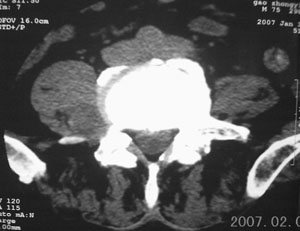

标题: CT8116:帮忙看这侧隐窝里是什么?男,75岁,腰周疼5-6年 [打印本页]

标题: CT8116:帮忙看这侧隐窝里是什么?男,75岁,腰周疼5-6年

男,75岁,腰周疼5-6年。别无症状。

右侧椎旁、侧隐窝软组织肿块,呈不规则双极征改变,椎体后外缘骨质弧形压迹,椎间孔扩大;考虑神经源性肿瘤,神经鞘瘤可能性大,需与神经纤维瘤相鉴别。

病变侧椎间孔扩大,椎体缘受压吸收;

考虑神经源性肿瘤,神经鞘瘤可能;

病变侧椎间孔扩大,椎体缘受压吸收,考虑神经源性肿瘤(神经鞘瘤可能)。